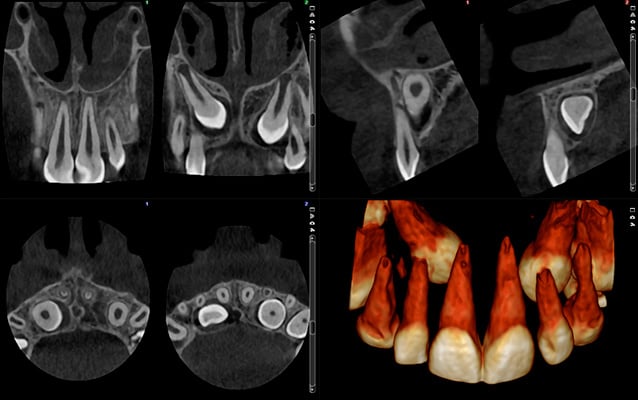

Immagini a ultra basso dosaggio – Caso ortodontico

Planmeca ProMax 3D - FOV Ø 85 x 50 mm. - Dimensioni voxel 400 µm - Dosaggio effettivo del paziente 4,0 µSv